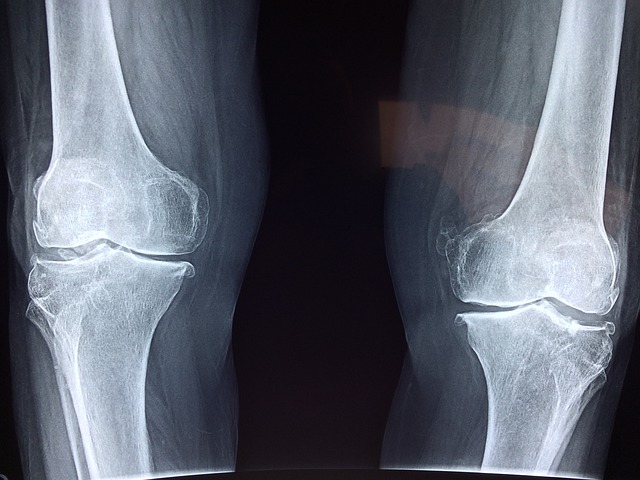

관절염은 관절의 염증으로 인해 통증과 부종을 유발하는 질환입니다. 이 질환은 여러 가지 형태가 있으며, 대표적으로 osteoarthritis(퇴행성 관절염)와 rheumatoid arthritis(류마티스 관절염)이 있습니다. 두 종류 모두 관절에 영향을 미치지만, 그 발생 원인과 증상은 다르게 나타납니다.

퇴행성 관절염은 일반적으로 나이가 들면서 발생합니다. 이 형태의 관절염은 관절의 연골이 마모되면서 점차 악화되는 현상인데요, 이는 오랜 시간 동안의 반복적인 스트레스나 과사용으로 인해 발생할 수 있습니다. 퇴행성 관절염은 무릎, 엉덩이, 손가락에 주로 발생하며, 증상으로는 통증, 뻣뻣함, 움직일 때 소리가 나는 등의 특징이 있습니다.

류마티스 관절염은 면역 시스템이 자기 자신의 관절을 공격하게 만드는 자가면역 질환입니다. 이로 인해 관절이 붓고, 심한 경우에는 관절의 구조와 기능에까지 영향을 줄 수 있습니다. 류마티스 관절염은 주로 양쪽에서 동시에 발생하며, 초기 징후로는 피로감, 불쾌감, 그리고 오후부터 저녁에 나타나는 관절 통증 등이 있습니다.